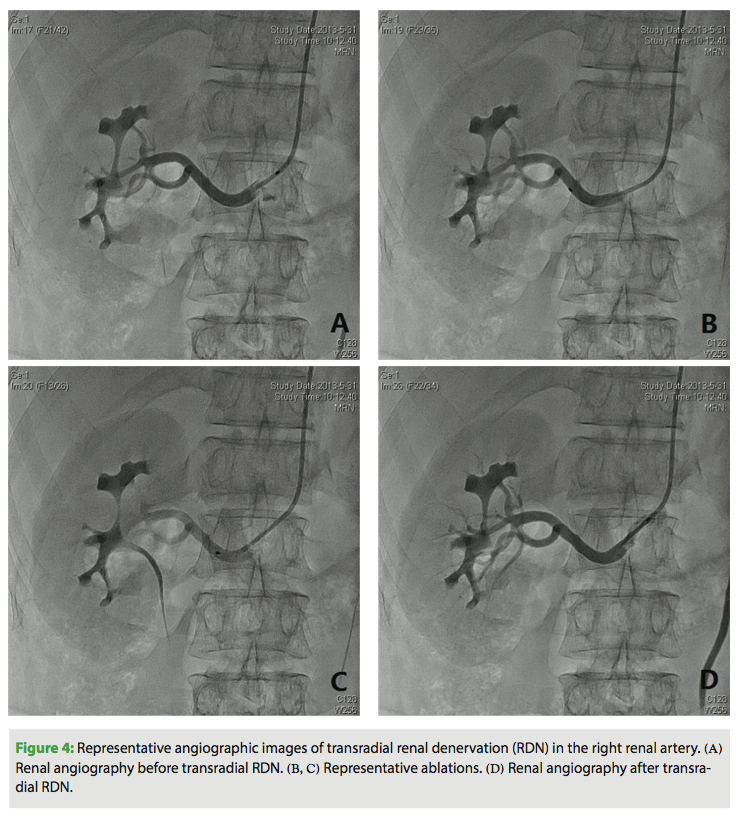

Under local anesthesia, using a modified Seldinger technique, a 6 Fr introducer sheath (Cordis Corporation) was inserted into the radial artery. A heparin bolus of 3000 units was administered intravenously and a continuous infusion of fentanyl and midazolam was started (5 µg and 0.2 mg/kg/h, respectively) and maintained until completion of RDN. In each case, the operator could easily advance a 6 Fr MPA1 guiding catheter (125 cm; Cordis Corporation) to the orifice of the renal arteries over a 0.035˝ HiWire angled hydrophilic guidewire (Cook Medical) (Figure 2). Renal angiography was first performed to further assess renal anatomy and dimensions (Figures 3A and 4A). Then, a 155 cm Iberis ablation catheter (AngioCare) was inserted and its tip was positioned proximal to the bifurcation of the renal artery. As previously described,3,4 4-8 ablations of 8 W or less and lasting up to 120 s each were performed along the length of the renal artery, separated both longitudinally and rotationally (Figures 3B, 3C, 4B, 4C). The procedure was repeated in the contralateral artery.

Supplementary doses of fentanyl or midazolam were given at the discretion of the anesthetist and guided by the clinical and hemodynamic responses. After the procedure, renal angiography was performed to evaluate changes in the renal arteries (Figures 3D, 4D). The access site sheath was removed immediately after the procedure, and a single tourniquet was pulled tight over the radial puncture site. Pressure was maintained on the puncture site for approximately 6 hours. Patients were typically discharged the day after the procedure.